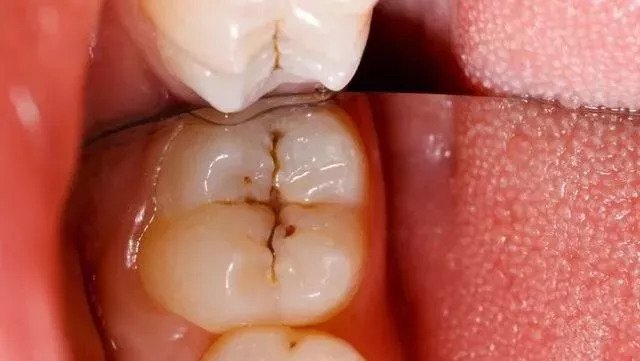

我们常说的后牙,学名第一磨牙和第二磨牙,是磨碎食物的主要牙齿,也是最坚硬,最大的牙齿。首先我们需要了解后牙窝沟点隙的结构,即发育沟。后牙的表面即咬合面,一般会有四个隆起角,由牙胚发育而成。四个隆起部位之间形成沟壑点隙。这些沟壑的形态不同,而这些沟壑最容易附着堆积污垢细菌,形成窝沟龋,窝沟龋形态千变万化,每个人的样子都不同,但大致都会有明显的黑线模样。

窝沟的形态与龋坏的进展速度是密切相关的。窝沟是不易清洁的,在窝沟发生龋坏时,损害是从窝沟侧面开始(釉柱和密度决定),最后扩展到窝沟底部,当窝沟龋进一步发展,达到牙本质层时,龋坏速度就会加快。直到腐蚀到牙髓,疼痛就开始了。

牙齿出现黑线预示着什么?一旦牙齿沟出现黑线,很不幸,说明你已经蛀牙了!不要单纯的以为那只是色素累积,早期蛀牙是没有龋洞的,平时饭后没有注意漱口,容易造成食物残渣堆积,给口腔细菌提供了营养,在唾液环境下,导致牙齿表面(牙釉质)被破坏。

早期的后牙有蛀牙是没有明显的龋洞,大多在咬合面有黑色的勾线,很多患者都以为那是色素沉着,洗牙时总是要求尽力把那洗去,殊不知那其实已经是龋坏。

1、蛀牙基本形成,沟壑内附着细菌,牙齿表面黑线形成。

2、蛀牙侵蚀到牙本质内部,吃东西遇到冷热酸甜会感到不适,也由原来的黑线发展成较大的蛀洞。

3、蛀牙继续向下发展侵犯到牙髓,这时候就出现明显的疼痛,龋洞更大,继续发展下去,整个牙齿就烂掉了。